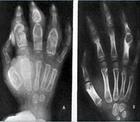

長短骨骨干結核很少見,其發病順序為股骨、脛骨、橈尺骨干、肱骨干和腓骨干。10歲以下的兒童最多,且常為多發,30歲以上的則很少見。在兒童,病變多波及幾個長骨干,常并發肺結核或其他骨結核。病人有明顯的全身癥狀。單發病例的全身癥狀不明顯,局部癥狀也輕微。